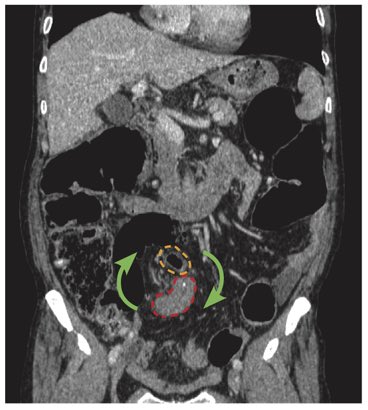

CTではS状結腸および口側の腸管に拡張を認めます(青矢印)

また、S状結腸の口側および肛門側の2カ所に嘴状の狭窄(Beak Sign)がみられます。(黄矢印・赤矢印)

CT冠状断ではS状結腸間膜が渦巻き状に描出されるwhirl sign(緑矢印)を認め、捻転をもっとも考えます。